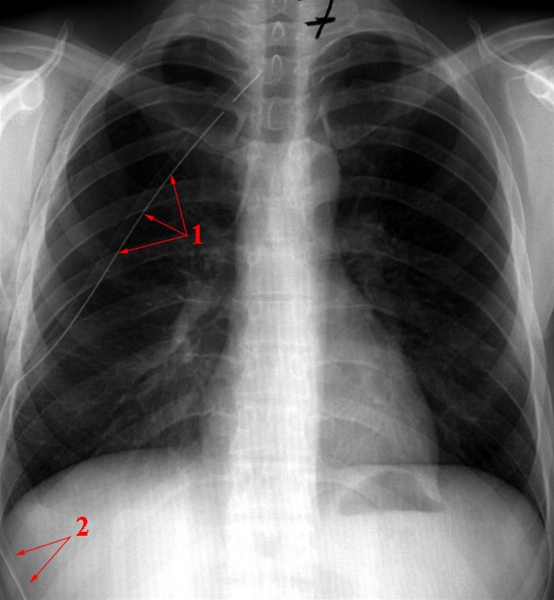

Lunger, røntgen, behandlet ventilpneumothorax

Billedet viser ophævelse af pneumothorax med pleuradrænage (1 og 2).